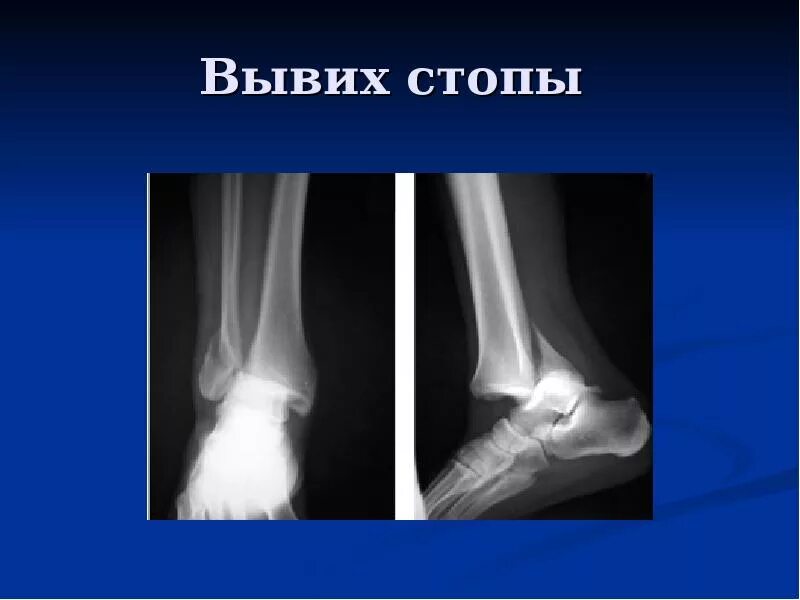

Вывих сустава стопы